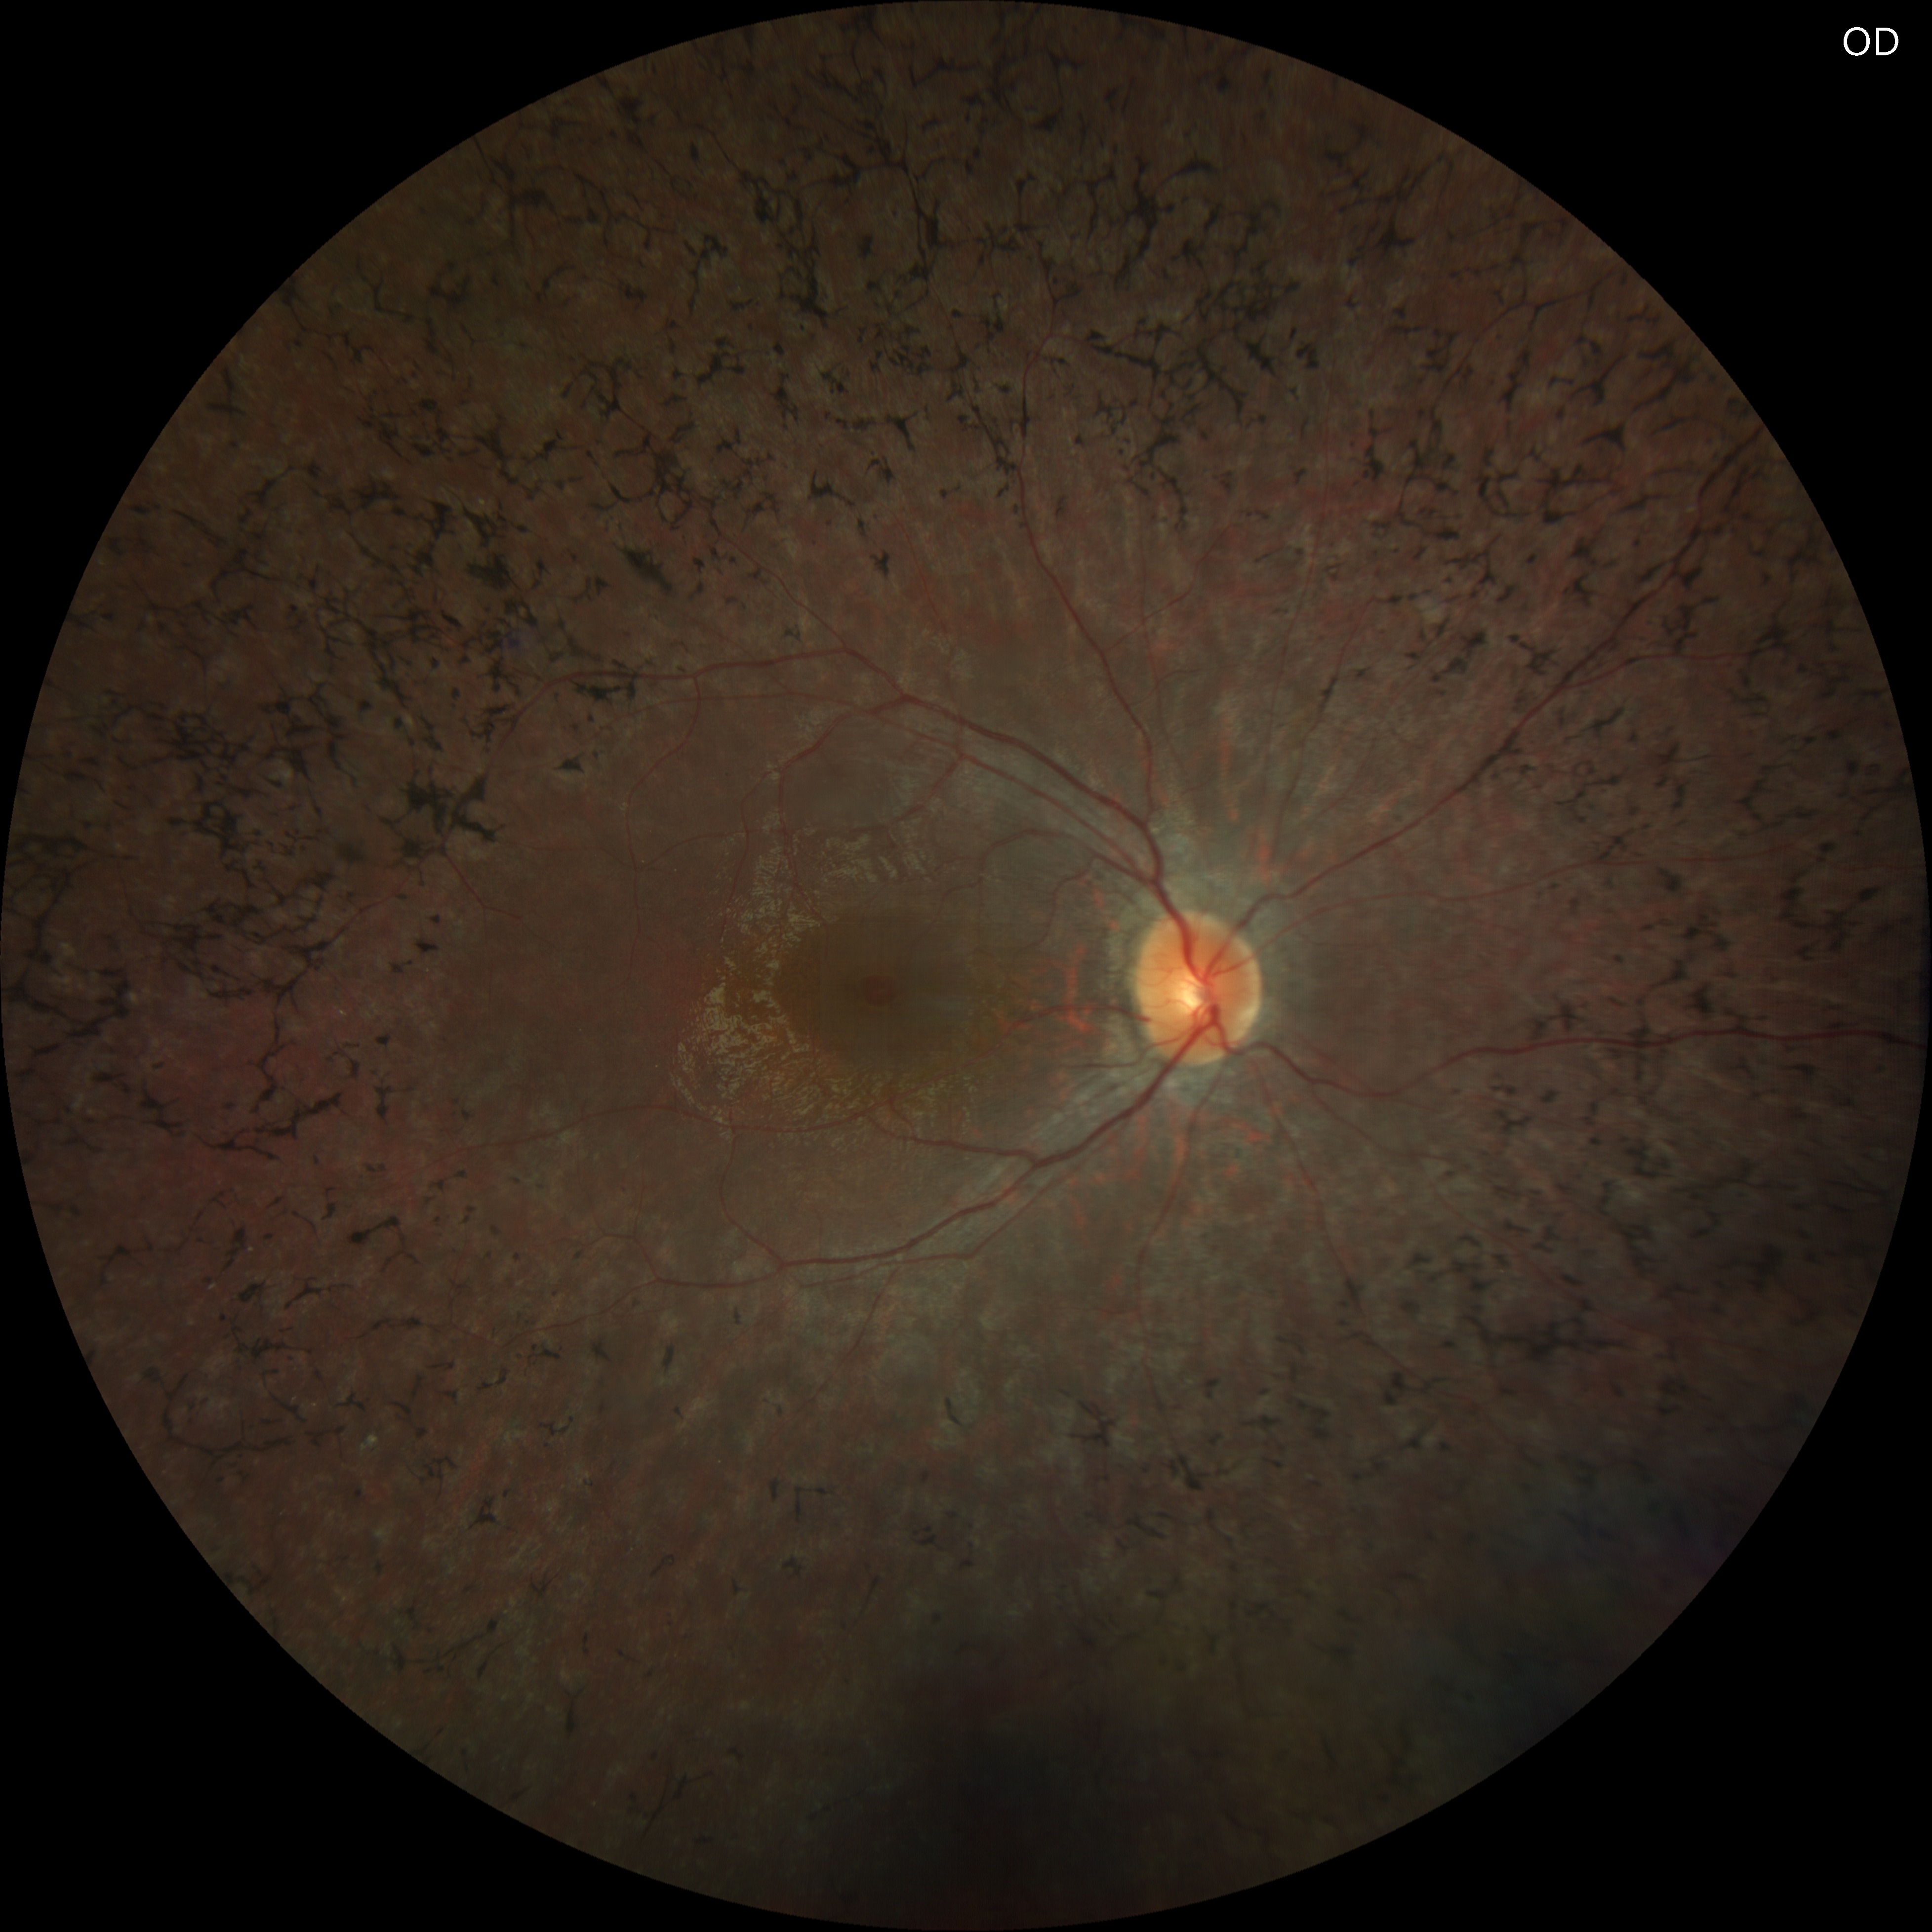

Fundus images showed mildly attenuated retinal vessels, widespread bone spicule–like pigmentary changes in the midperipheral retina and abnormal foveal reflex in both eyes.

A clinical diagnosis of Usher syndrome was made based on the history (poor night vision and hearing impairment since childhood), clinical findings (peripheral vision loss, mid-peripheral bony spicules, and arteriolar attenuation), and investigative results (optical coherence tomography, electroretinography, and pure tone audiometry).

Usher syndrome is an autosomal recessive disorder combining congenital sensorineural hearing loss with progressive retinal degeneration (retinitis pigmentosa). Fundus findings typically include bone spicule pigmentation, arteriolar attenuation, and optic disc pallor. Optical coherence tomography often reveals thinning of the outer retinal layers with loss of the ellipsoid zone, sparing the fovea in early stages. Full-field electroretinography demonstrates markedly reduced or extinguished scotopic and photopic responses. Early recognition allows appropriate genetic counseling, auditory rehabilitation, and multidisciplinary management.